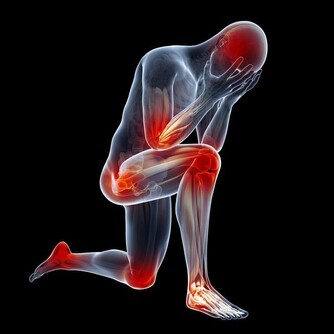

*****1、肢體發麻*****

如果起床時發現肢體有麻木感,不要認為是小毛病。肢體發麻是很多慢性疾病會發出的信號,例如高血壓、糖尿病、高血脂症,這些類型的疾病在發展過程中指標不正常,無形中會影響血管,神經功能,如果局部的循環出現障礙,肢體需要的營養物質,血液無法及時提供,會出現不良症狀,其中較常見的特徵是肢體麻木。

發現以上信號需要及時檢查,和糖尿病有關合理使用胰島素或者降糖藥物來改善,如果和血壓高或者高血脂症來襲有關,對症用藥以及改掉不良的生活習慣可以慢慢緩解。